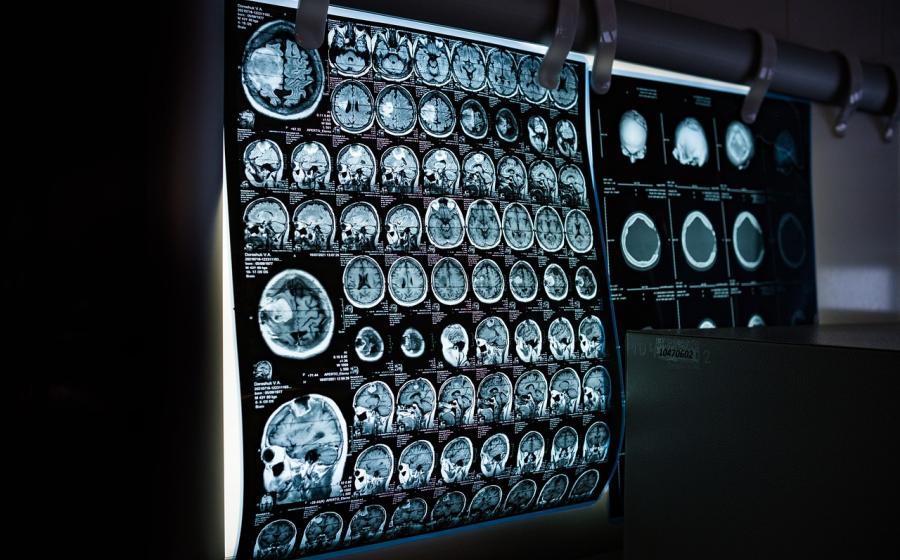

Přišla jsem k vám se spoustou potíží, které žádný lékař nedokázal vyřešit. Magnetická rezonance ukázala několik ložisek na mozku, která byla označená za nespecifická.

Larvy tasemnice mohou tvořit cysty v kterékoli části těla, včetně mozku. Tyto cysty mohou způsobit slepotu, ochrnutí a smrt. Jedním z hostitelů může být i člověk.